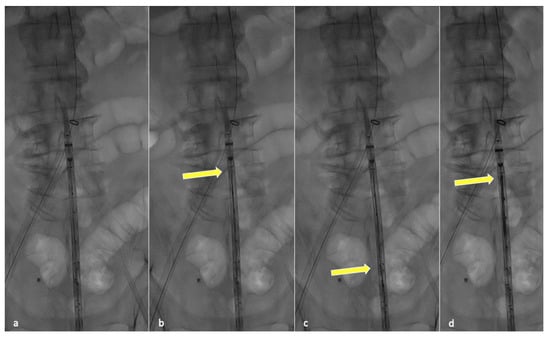

In order to perform partial endograft deployment, the device should be prepared before insertion by advancing, under fluoroscopy, all four dedicated 400 cm long 0.018″ non-hydrophilic guidewires through the corresponding microcatheters until their proximal end reaches the cranial graft’s edge (Figure 1).

Anticipating this guidewire placement prevents the inability to do so once the endograft is partially released, avoiding increased friction inside the constricted pre-loaded microchannels.

Figure 1. Fluoroscopic check during guidewire anticipated advancement. Graft leaning on patient body (a), yellow arrow pointing at the tip of the first positioned guidewire (b), second guidewire advancement (c) and final results after all guidewires have been correctly advanced (d).